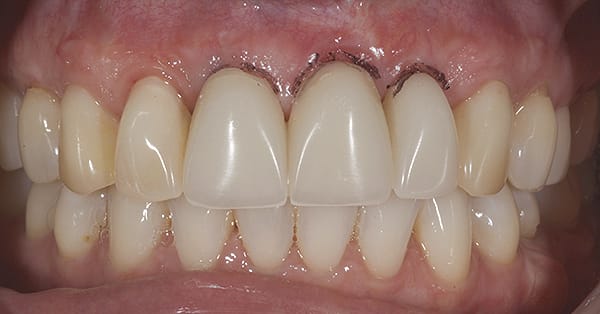

Although prosthodontists are capable of saving many complicated implant cases, the clinical results may still remain esthetically compromised. As opposed to heroic attempts to restore a misaligned implant, there are times when implant removal is a better solution. In the challenging case depicted in Figure 1 through Figure 4, it was determined that the implant, as positioned, could not be adequately restored. Two options were considered: implant removal and replacement with a properly positioned implant and implant replacement or submergence followed by the fabrication of a 3-unit fixed partial denture. The fixed partial denture would take advantage of utilizing tooth No. 8 as an abutment after removing the existing crown but would necessitate involving the virgin tooth No. 10. The surgical/prosthetic team in consultation with the patient elected to remove the implant and place a second implant. The implant was removed and a new implant was placed in the correct vertical and horizontal position using CT-guided surgery.